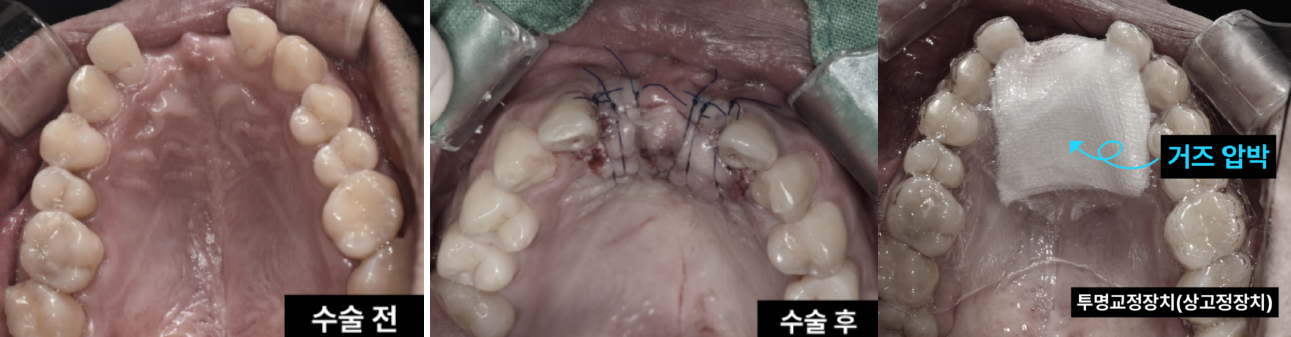

최소 침습으로 동시에 해결! 과잉치 제거&임플란트 이백점치과에서는 환자분의 부담을 줄이면서도 최상의 결과를 위해, 과잉치 제거와 동시에 임플란트 식립까지 한번에 진행하기로 치료 계획을 세웠습니다. 1. 과잉치 제거 : 입천장 잇몸을 조심스럽게 열고 잇몸 뼈를 최소한으로 삭제하여 과잉치를 안전하게 발치했습니다. 2. 동시 임플란트 식립 : 과잉치 제거 후 바로 그 부위에 임플란트를 정교하게 식립하여 수술 횟수와 치료 기간을 단축했습니다.

최소 침습으로 동시에 해결! 과잉치 제거 & 임플란트 식립 이백점치과에서는 환자분의 부담을 줄이면서도 최상의 결과를 위해, 과잉치 제거와 동시에 임플란트 식립까지 한 번에 진행하기로 치료 계획을 세웠습니다. 1. 과잉치 제거: 입천장 잇몸을 조심스럽게 열고 잇몸 뼈를 최소한으로 삭제하여 과잉치를 안전하게 발치했습니다. 2. 동시 임플란트 식립: 과잉치 제거 후 바로 그 부위에 임플란트를 정교하게 식립하여 수술 횟수와 치료 기간을 단축했습니다.

꼼꼼한 마무리와 빠른 회복 수술 후에는 잇몸이 벌어지지 않도록 꼼꼼하게 봉합하는 것이 매우 중요합니다. 이백점치과는 숙련된 노하우로 섬 세한 봉합을 진행하여 빠른 회복을 유도합니다. 당일 구강 스캐너를 활용해서 환자분에게 딱 맞는 투명교정장치를 바로 만들어드렸어요. 덕분에 수술 부위 보호와 치아 이동 방지까지! 회복 기간도 더 편안하게 보낼 수 있었답니다.